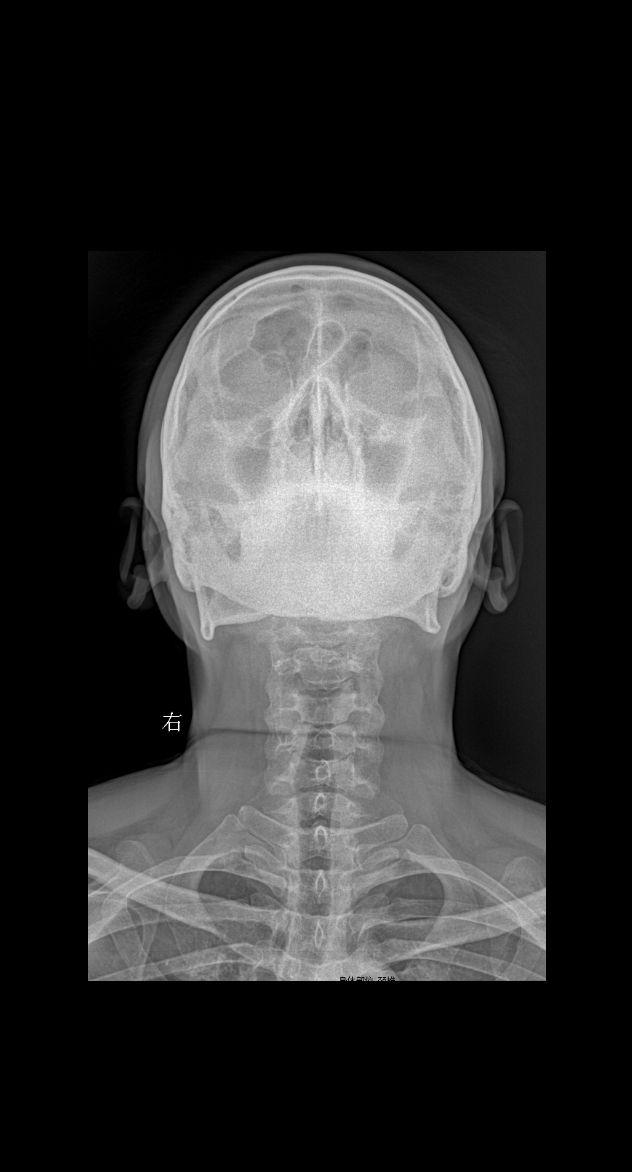

颈部疼痛 头晕 就诊

2025-04-17 17:02

颈椎疼痛 头晕 就诊

2025-04-19 16:41